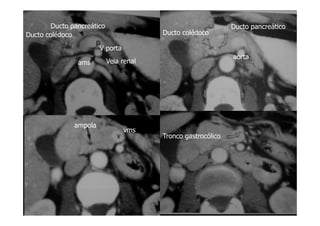

Ao nível da cabeça pancreática e do processo uncinado(u),a junção

do ducto pancreático comum com o ducto biliar comum(seta curva) é

definida.A artéria mesentérica superior situa-se anterior a aorta e

posterior a junção do colo e corpo do pâncreas.

Ao nível do colo pancreático,é visível o ducto pancreático

principal(seta aberta).

A v. porta situa-se imediatamente posterior ao colo do pâncreas e

lateral à artéria mesentérica superior.

(Ponta de seta)Artéria pancreato duodenal antero superior.

Ao nível do corpo pancreático observa-se um curto segmento do ducto

pancreático(ponta de seta).

Veia renal esquerda(seta curva).

Corpo e cauda pancreática(seta aberta maior).

Vv hepáticas não contrastadas.

Ducto pancreático

V porta

ams

Ducto colédoco Ducto colédoco

aorta

Veia renal

ampola

vms

Tronco gastrocólico